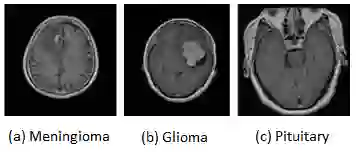

Brain tumor is the most common and deadliest disease that can be found in all age groups. Generally, MRI modality is adopted for identifying and diagnosing tumors by the radiologists. The correct identification of tumor regions and its type can aid to diagnose tumors with the followup treatment plans. However, for any radiologist analysing such scans is a complex and time-consuming task. Motivated by the deep learning based computer-aided-diagnosis systems, this paper proposes multi-task attention guided encoder-decoder network (MAG-Net) to classify and segment the brain tumor regions using MRI images. The MAG-Net is trained and evaluated on the Figshare dataset that includes coronal, axial, and sagittal views with 3 types of tumors meningioma, glioma, and pituitary tumor. With exhaustive experimental trials the model achieved promising results as compared to existing state-of-the-art models, while having least number of training parameters among other state-of-the-art models.